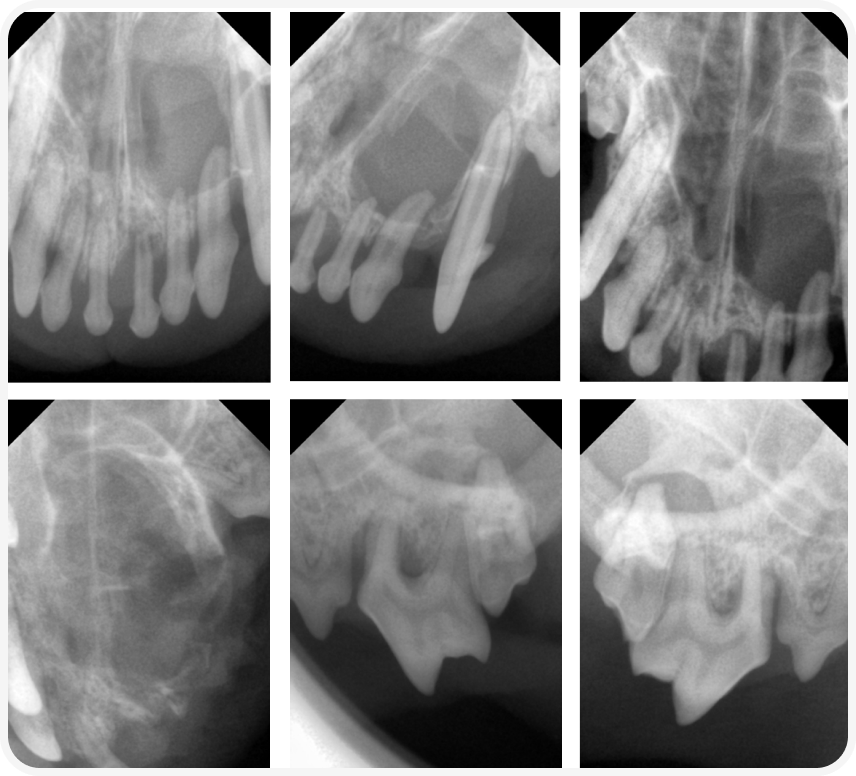

При осмотре в анестезии был подтвержден комплекс стоматологический патологий (гингивит, пародонтит). Провели дентальную рентгенографию с помощью визиографа. Снимки прилагаются.

При исследовании обнаружились зубы с признаками пульпита (расширенный корневой канал), а также связанное с ними четко очерченное просветление в области 202,203,204.